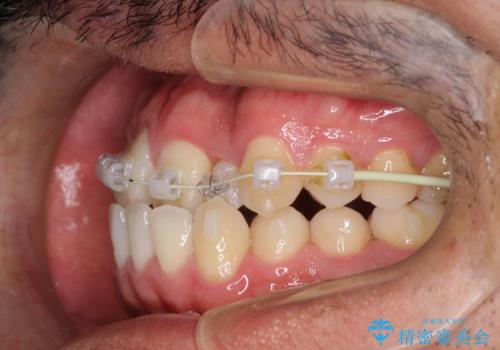

患者様がマウスピースを希望されていましたが、上の前歯のがたつきを先にワイヤーで改善する方が早く治療が終了することが可能であるとお伝えし、上顎のみ半年間ワイヤーで治療を行いました。

マウスピースのみでの治療も可能でしたが、治療期間がもう少し延長していた可能性があります。